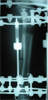

Had a fall and developed varus

deformity over distraction site

Post

Op

Varus deformity over distraction site